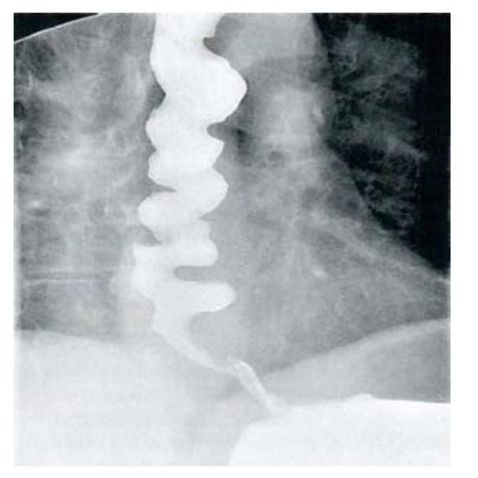

65. 28歲女性因8週的下腹絞痛合併腹瀉病史,接受進一步評估,她每天排便6至10次,其中有一至二次在半 夜,大便特徵為loose to watery with intermittent blood streaking。另外她有噁心及食慾變差現象,但無嘔 吐、發燒,也無服用藥物病史。身體檢查:體溫:37.8℃,血壓100/54 mmHg、脈搏96/min,腹部呈 現diffuse tenderness但無rigidity, guarding或rebound pain。大腸鏡檢查在升結腸、橫結腸及降結腸有如 附圖之發炎病灶,但是terminal ileum及rectum並無發炎現象,下列何者為最可能之診斷?

(A) Collagenous colitis (B) Crohn colitis (C) Ischemic colitis (D) Ulcerative colitis (E) Tuberculous colitis